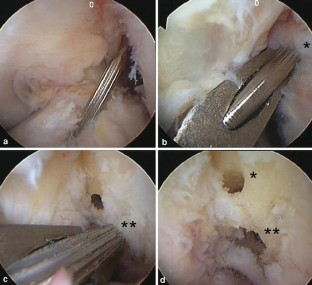

Fig. 4